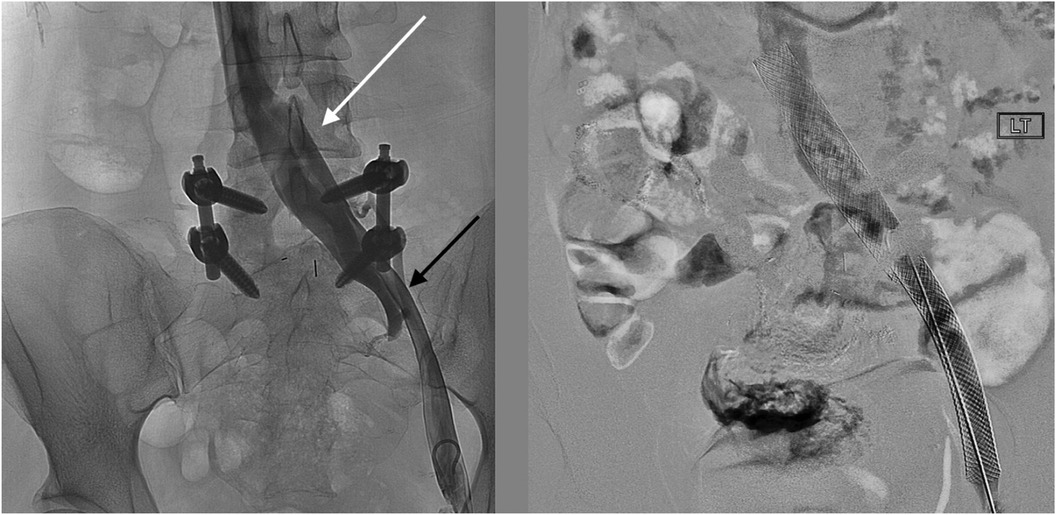

The patient underwent treatment at AMITA Hinsdale Hospital (Hinsdale, IL, USA). Under moderate sedation, the patient underwent traditional transcatheter venography (Figure 2). This, along with intravascular ultrasound (IVUS), confirmed significant (25) left common iliac vein stenosis by an overlying common iliac artery of greater than 50% (25) (Figure 3). She was initially treated with placement of a left iliac vein stent. Post procedure, she was prescribed clopidogrel for 30 days. 30–40 mm Hg waist-high compression hose were ordered, and she was advised to hydrate daily with 100 oz of electrolyte drinks. She underwent a routine clinical and imaging follow-up at 1 and 6 months. Confusion and dizzy spells were reported as alleviated at 1 month, but still some diminished cognitive clarity persisted. At 6 months, she reported improvement in cognition to a point where she reenrolled in graduate studies and resumed driving. According to her neurologist, she was having significantly fewer headaches and fatigue was reported to be reduced. Slight dizziness persisted, and she was started on a short course of midodrine. Dyspareunia persisted. She was subsequently administered a percutaneous ultrasound-guided injection of the vaginal wall and vulvar varices with 0.5% sotradecol foam using the Tessari technique (13). There were no immediate procedural complications, and her dyspareunia resolved after 3 months. At 12 months after iliac vein stenting, repeat neuropsychiatric testing (with the same examiner) showed her memory at the 95th percentile. Her full-scale IQ increased modestly. The Beck Depression Inventory II score moved to the normal range. The overall impression was “normal exam” (Supplementary Table 1). At 18 months after stenting, her dizziness returned, and dyspareunia reappeared. An ultrasound suggested a developing right iliac vein stenosis. Subsequently, a CT venogram showed the left stent pressing upon an already partially compressed right common iliac vein (Figure 4). She then underwent placement of a right-sided iliac vein stent. She was again prescribed clopidogrel, but for only 3 months, and again advised to drink 100 oz electrolyte solution daily and wear waist-high compression hose.

Figure 2

Medical imaging showing two X-ray views. The left image displays spinal hardware with arrows indicating specific areas of interest. The right image shows a stent-like structure in a vessel, marked by the label \

Figure 2. Venographic images at the time of procedure from a left common femoral vein access show (left) an en-face widening of the central left common iliac vein (white arrow) and the stenotic left external iliac vein (black arrow). After stenting (right), the affected areas are covered by the self-expanding stents.